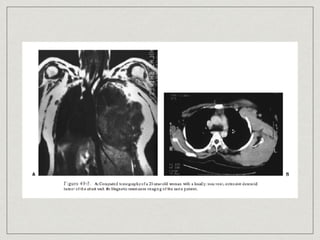

CT (Gold standard)

MRI

PET-CT

Diagnosis CT (Gold standard) MRI PET-CT Tissue diagnosis: Needle biopsy, Excisional biopsy, Incisional biopsy